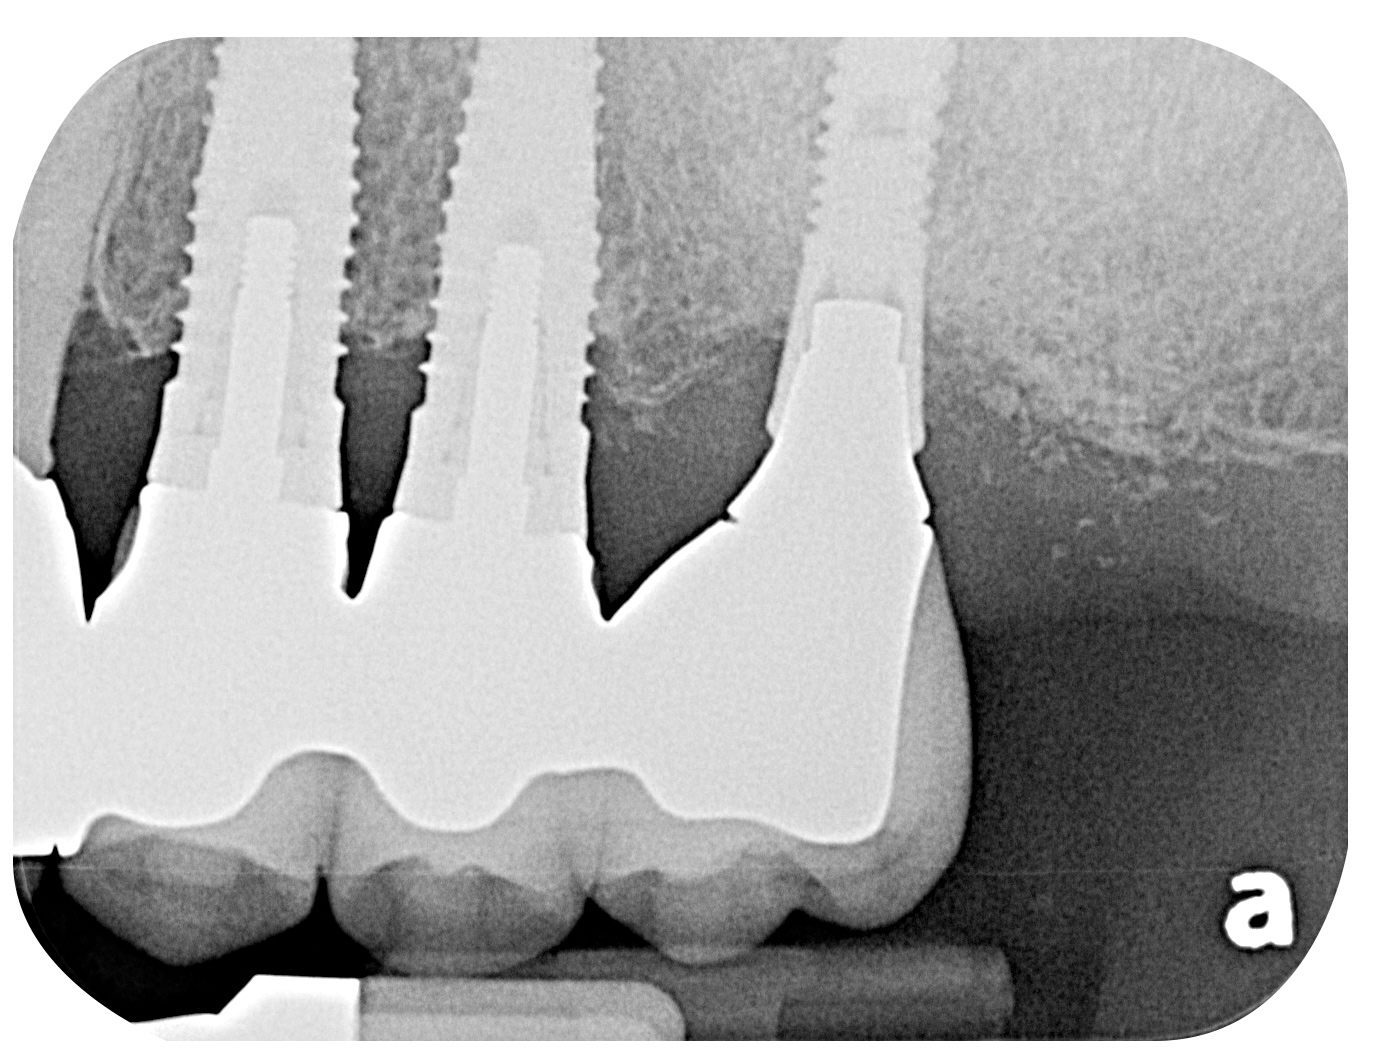

Dental implants have revolutionized the way in which clinicians treat and restore partially and fully edentulous patients and have demonstrated success for managing a broad range of clinical dilemmas. While implants have been highly predictable and have achieved long-term success, they are not immune from complications associated with improper treatment planning, poor surgical and prosthetic execution, material failure, and inadequate or infrequent maintenance. Among these problems are the biologic complications of peri-implant mucositis and peri-implantitis, which are inflammatory conditions in the soft and/or hard tissues surrounding dental implants (Figure 1 through Figure 4).1,2